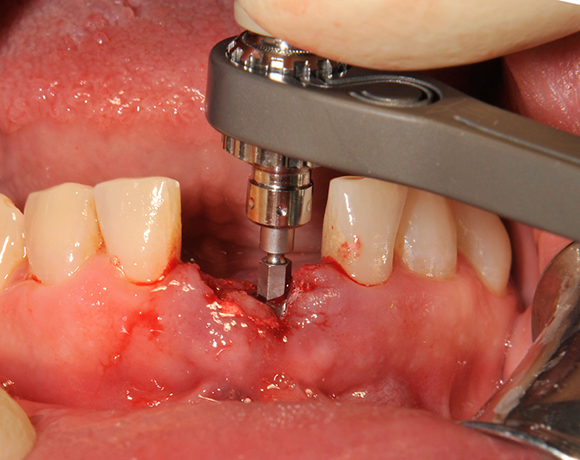

Die Keramikimplantate der Fa. Dentalpoint lassen sich auch zur Sofortimplantation verwenden. Das bedeutet, dass nach Extraktion nicht beherdeter Zähne direkt die Implantate gesetzt werden können.

Im vorliegenden Patientenfall wurden die beiden nicht erhaltungswürdigen, mittleren Unterkieferschneidezähne durch zwei Vollkeramikimlpantate ersetzt.